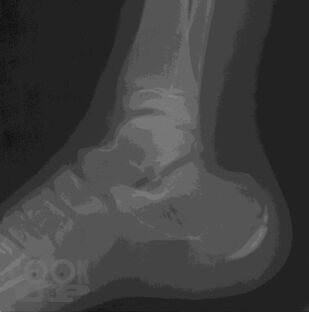

В учебном пособии представлены общие положения о развитии и анатомии опорно-двигательного аппарата, методы лучевой диагностики и показания для их использования при исследовании костей и суставов, изложены основы посиндромного подхода к диагностике заболеваний костно-суставной системы, основы диагностики травматических повреждений.